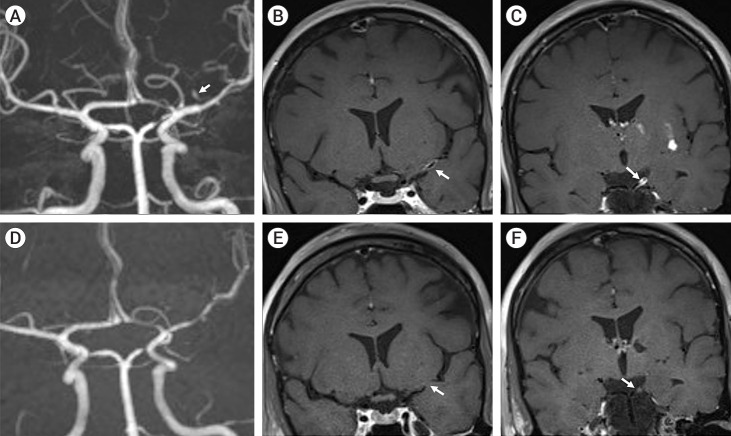

Primary Angiitis of the Central Nervous System (PACNS) is an uncommon disease with kaleidoscopic clinical manifestations. Ischemic strokes are commoner than their hemorrhagic counterpart. Intracranial pseudoaneurysms are rarely reported in PACNS cohorts. We hereby describe the case of a 39-year-old female, who presented for evaluation of acute onset of left middle cerebral artery (MCA) ischemic stroke, with cerebral angiogram showing multifocal stenosis and irregularities in intracranial blood vessels with an aneurysm arising from the lenticulostriate branch of the left MCA M1 segment. A diagnosis of probable PACNS was made and patient initiated on immunomodulatory treatment with corticosteroids. 12 weeks follow up neuroimaging studies revealed resolution of the previously described intracranial aneurysm, thereby postulating the possibility of a pseudoaneurysm related to the underlying angiitis.